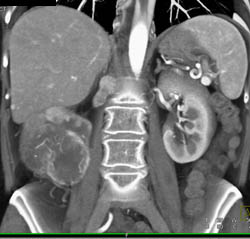

Clot in Portal Vein (PV) and Splenic Vein